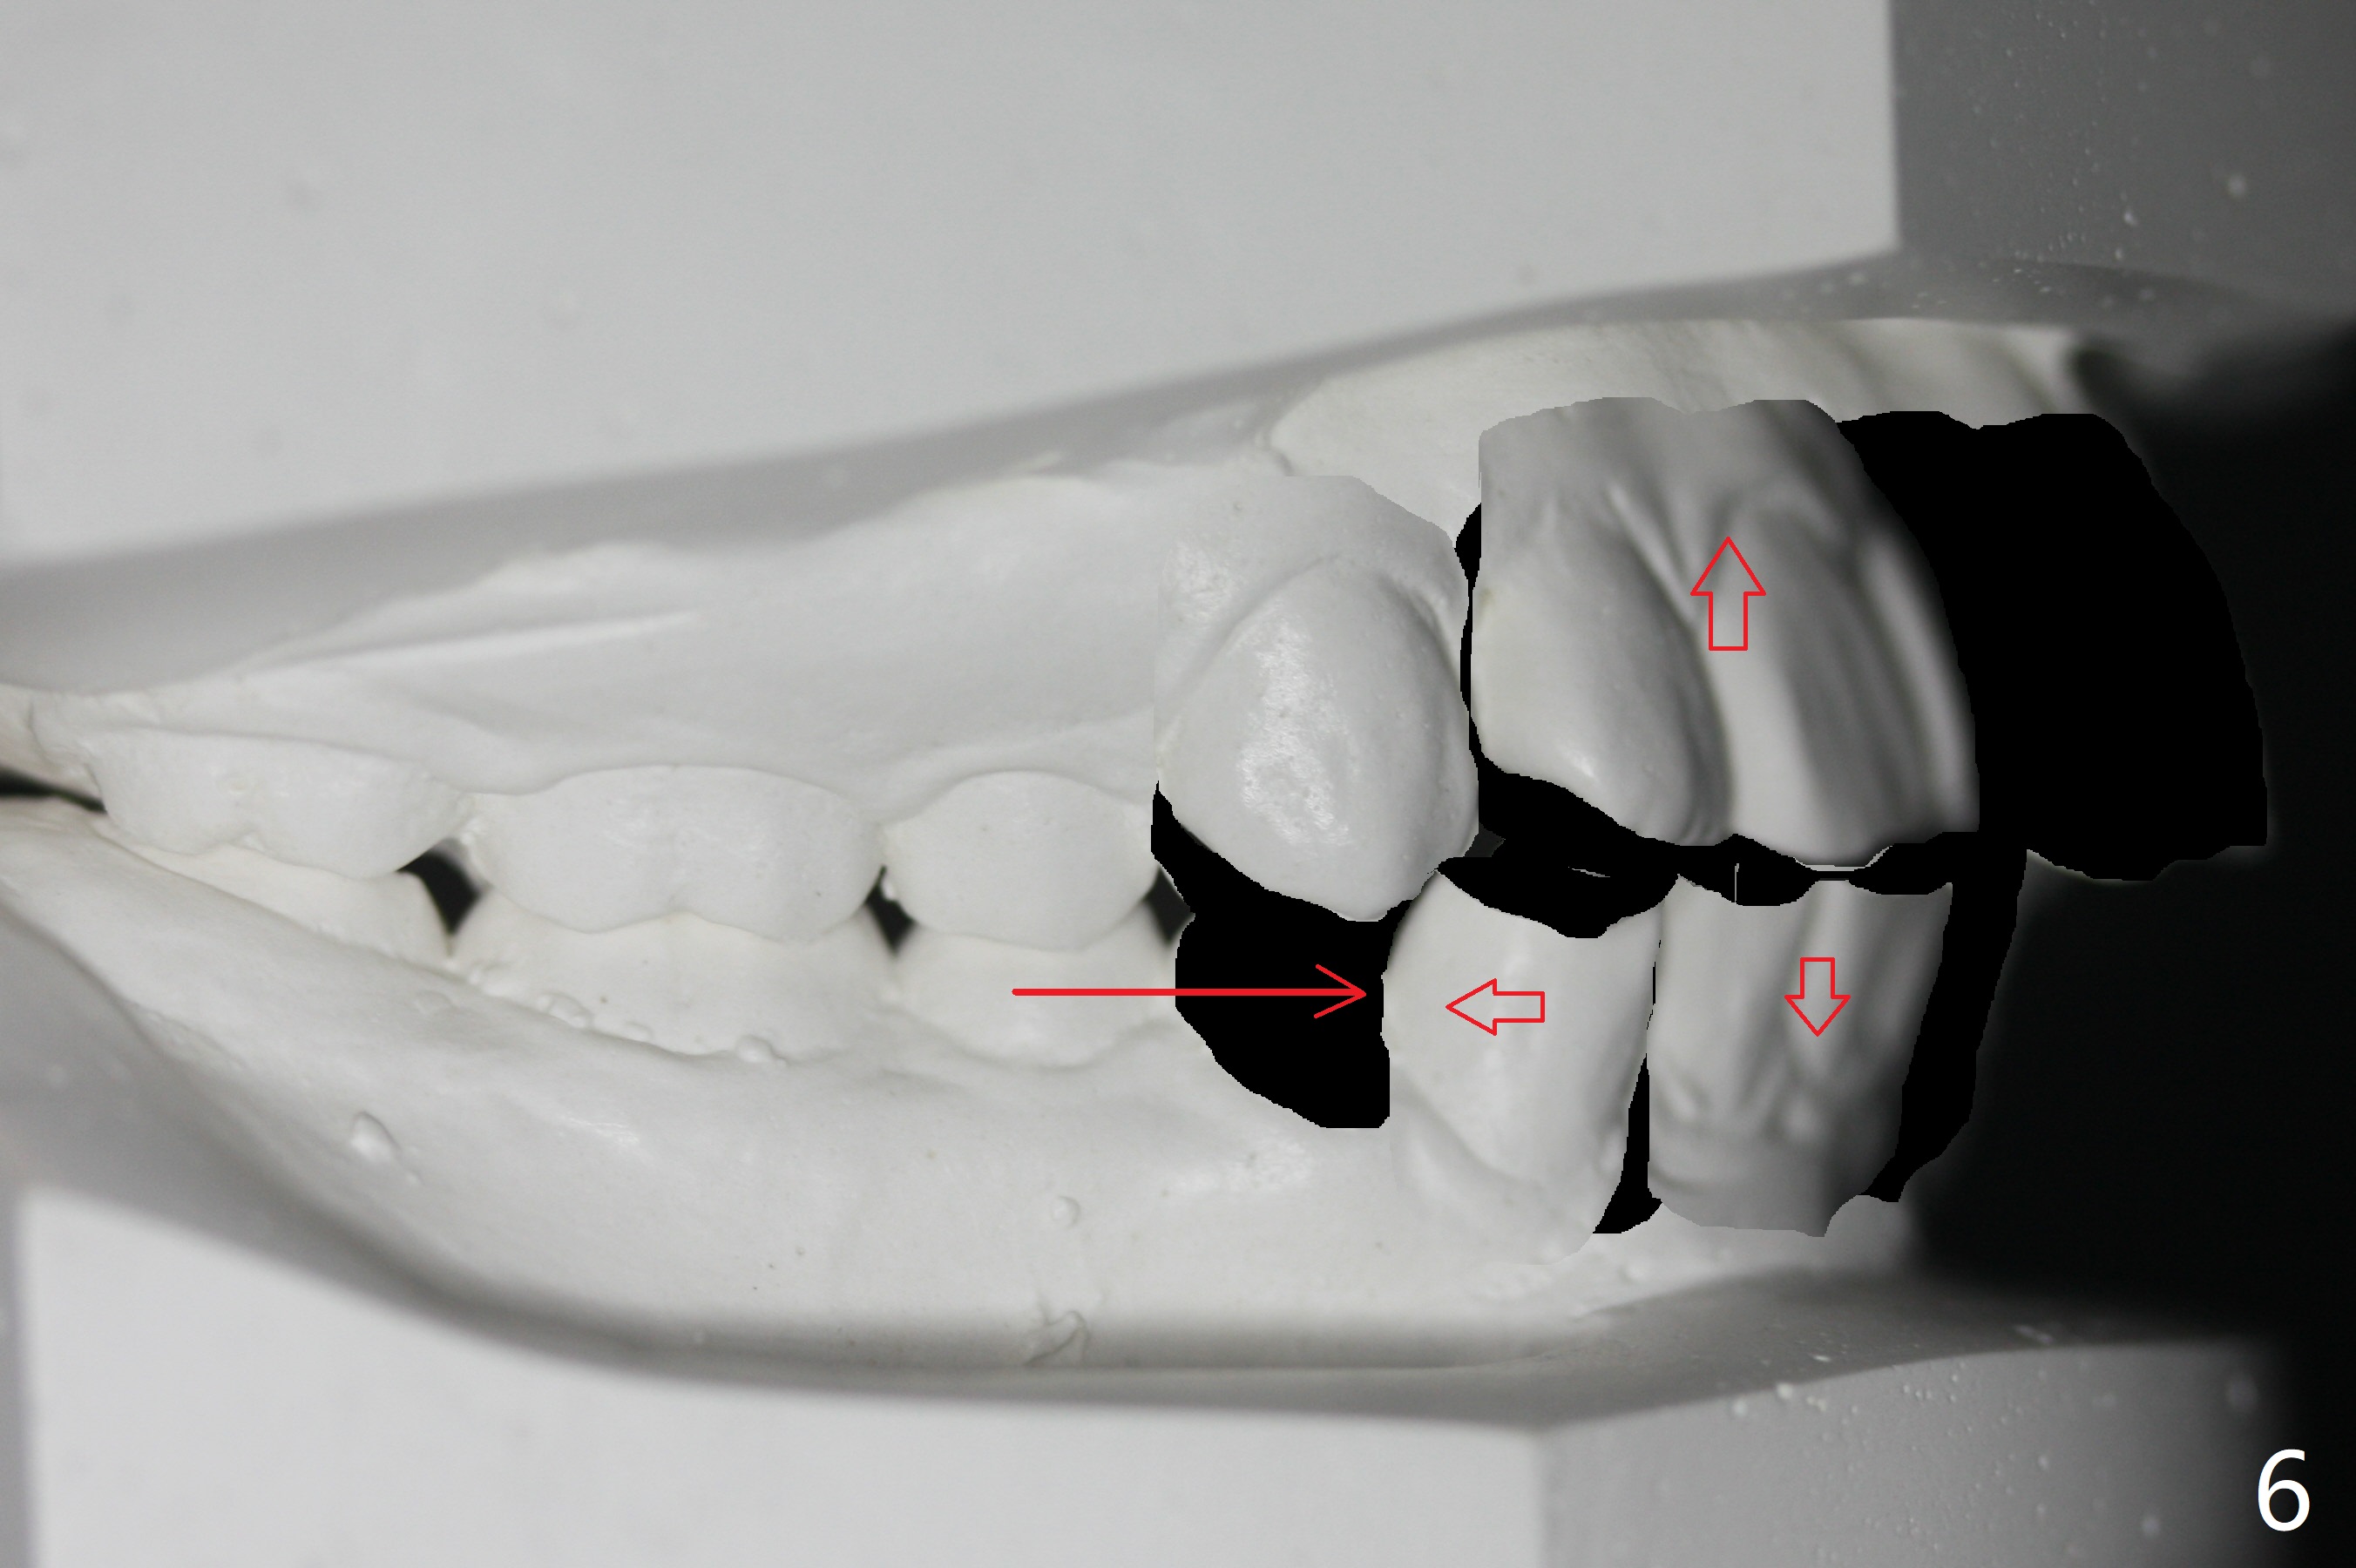

I Malocclusion

The 1st step to correct severe Class II Division I malocclusion (Fig1) is extraction of 4 of the 1st bicuspids (Fig.2 X). Following placement of 16x16 wires, start Class II retraction (Fig.3 red line) as well as distalization of U3 (Fig.4). When canine Class I relation is established (Fig.5 horizontal arrow (using power chain between L3/5)), arch wire sequence should be able to intrude the incisors (vertical arrows). Finally the lower 2nd bicuspid and molars are mesialized (Fig.6 arrow).